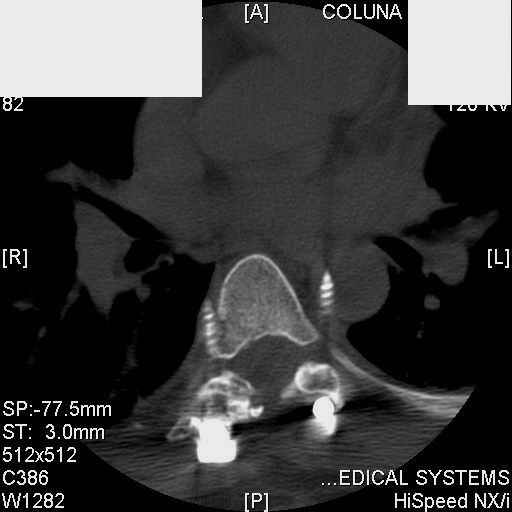

dear Mark, all the details are not yet available but the patient is coming to see us foradvice. We probably will see him in the early new year. i thought that the 4th picture showedthe screw to enter the aorta? He is a victim of a motor vehicle crash and thoracic vertebralfracture which appears healed. He was posteriorly decompressed and this device inserted. asyou say there isno evidenece that any of the fixation enters the bodies via the pediclesistead they have passed thru and their end are no where near where they ought to be. If I amcorrect (I would prefer not to be) the aortic intima has been breached by the screw. When thetime comes to take the screw out I thought we should have control of the aorta.What do you think?

Tom: I strongly doubt that the aorta is involved. When these screws are put in, they firstput in a probe, then a tap, then the screw. If the aorta was punctured, they would have knownat the time. You might call the original surgeon (if in fact he is a real doctor) and get hisfeedback. The additional morbidity of a prophylactic thoracotomy would be a higher pricethan I would be willing to subject my patient to. Besides, it would be exceptionallydifficult to control the aorta at this point, especially if you tried to specifically getenough control to be able to put sutures in the back wall. Of course, difficulty of doingsomething isn't necessary a reason not to do it if you think it is necessary. I just think itis highly unlikely that the aorta is injured. I showed the case to both a thoracic surgeon anda neurosurgeon. The thoracic surgeon suggested getting an arteriogram to see if the aorta isinvolved. The neurosurgeon agreed that the hardware should be removed.

Mark Thank you. He is scheduled for a angio prior to transfer here. I keep going back to lookat that fourth image and although it is tough to believe the wall of the aorta seems toencompass the distal 1/2 of the screw. I have come to anticipate mal postion of screws thathave been inserted in hospitals that perhaps may not have the highest quality of equipment,including the human and radiological components. That having been said this case seems tosurpass the usual... one screw out of place or screwed into a disc etc. BTW I am notsuggesting that the screw was placed directly into the aorta but that moviment, pulse actionetc may have caused it to transgress the normal anatomical bounds without evident hemorrhage.

Подошли ангиограммы... Наслаждайтесь...

травматический обратный дивертикул аорты!